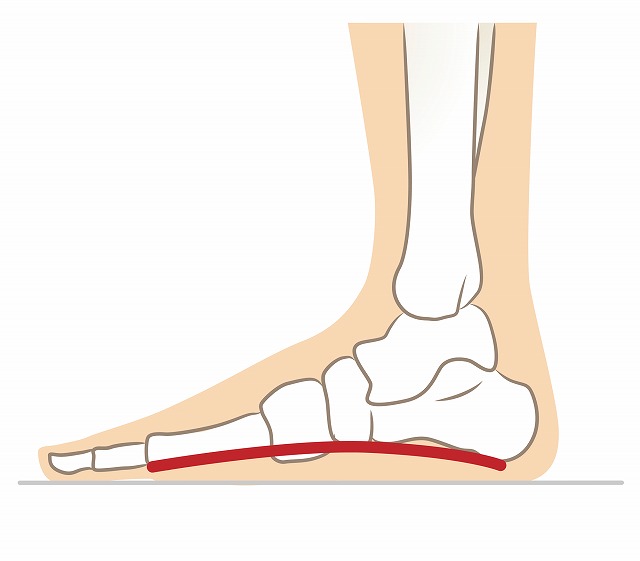

足底筋膜炎とは

足裏の筋肉への負荷による炎症や微小な断裂の繰り返しによって引き起こされる症状を、足底筋膜炎といいます。特に痛みを感じやすいのは歩き始めや立ち上がるときで、歩くにつれて痛みが軽くなるという症状が特徴です。土踏まずの慢性的な痛みや、歩き始めや立ち上がりの際の痛みがある場合、足底筋膜炎が疑われます。

足裏の筋肉への負荷による炎症や微小な断裂の繰り返しによって引き起こされる症状を、足底筋膜炎といいます。特に痛みを感じやすいのは歩き始めや立ち上がるときで、歩くにつれて痛みが軽くなるという症状が特徴です。土踏まずの慢性的な痛みや、歩き始めや立ち上がりの際の痛みがある場合、足底筋膜炎が疑われます。

足底筋膜炎の原因

スポーツや長い時間の立ち仕事の際は、常に足底筋が緊張してしまっています。足底筋膜炎は、スポーツや長時間の立ち仕事で足底筋が繰り返し使われることにより疲労が蓄積することが原因で引き起こされることがあります。

土踏まずは、身体への衝撃を吸収する機能を有しており、筋力の低下はその土踏まずへの負担を招きます。足底筋膜炎は、特に足裏や足指の筋力の低下による足底筋への負担によって誘発されます。